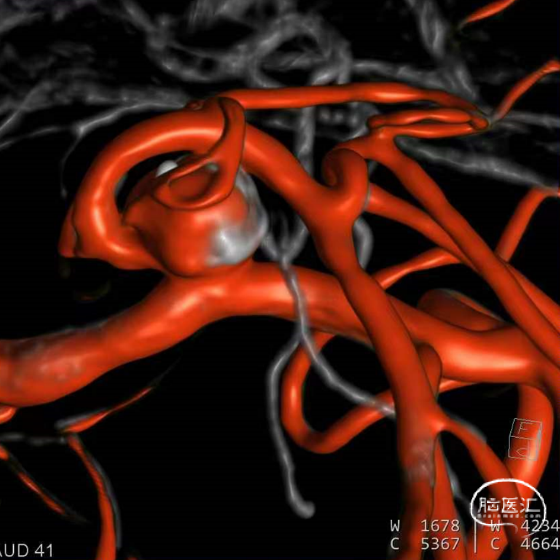

动脉瘤一:基底动脉末端动脉瘤,由左侧大脑后动脉与左侧小脑上动脉瘤夹角处动脉瘤形成且为不规则状;瘤体上有子囊形成,左侧小脑上动脉从近心端瘤颈处动脉瘤瘤体上发出,动脉瘤与载瘤动脉近直角。

经测量可得动脉瘤宽度平均值为8.88mm,动脉瘤最小高度为7.71mm,瘤颈约为4.03mm。参考尺寸选择表,选择WEB™ SL 10*5,VIA™ 33微导管。

缓慢推出WEB™从种子至萌芽状态,继续向瘤腔内远端缓慢推送WEB™至萌芽至开花间状态;将WEB™和VIA™送至瘤顶,固定WEB™推送杆回撤VIA™,WEB™完全释放。

经造影可见WEB™尺寸合适,贴合瘤壁,小脑上动脉分支,大脑后动脉分支等血流通畅。解脱后,再次造影和Dyna-CT评估,可见动脉瘤瘤腔内有明显造影剂滞留,小脑上动脉瘤显影良好,分支血管血流正常。

此为左侧大脑中动脉瘤,近端血管极为迂曲,瘤体有突出的子囊,动脉瘤与载瘤动脉有一定夹角,动脉瘤呈上窄下宽形状,M2段下干从瘤颈近端发出。

动脉瘤平均宽度5.41mm, 最小高度为3.71mm,瘤颈约为4.94mm,使用WEB™ SL 6*3mm瘤内扰流装置进行栓塞治疗。